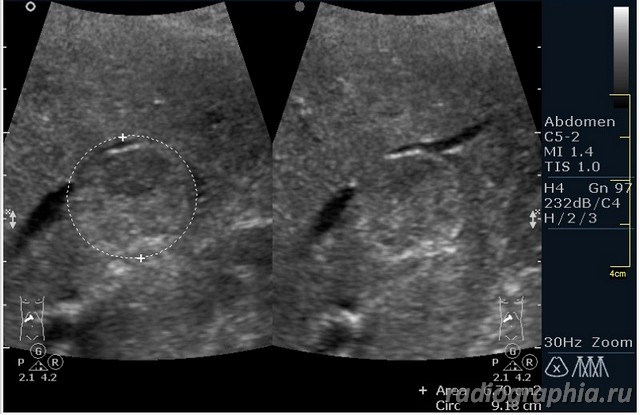

УЗИ печени. Женщина 37 лет. Жалобы на боли в эпигастрии; в печени обнаружено такое образование...

Считаю,что это опухоль,имеет неоднородную структуру,четкий контур,прорастает в сосуд(есть один такой скан) И,вообще,вся поверхность печени НЕСПОКОЙНАЯ,могут быть мелкие МТ.Интересно,что на КТ?

так и хочется назвать это метастазами но уж очень они красивые и доброжелательние по структуре (изоехогенные по отношению к структуре печени) и они больше компресирують чем проростают, склонен к ответу о доброкачественной гиперплазии. так что же на КТ?

гемангиома,рядом питающий сосуд